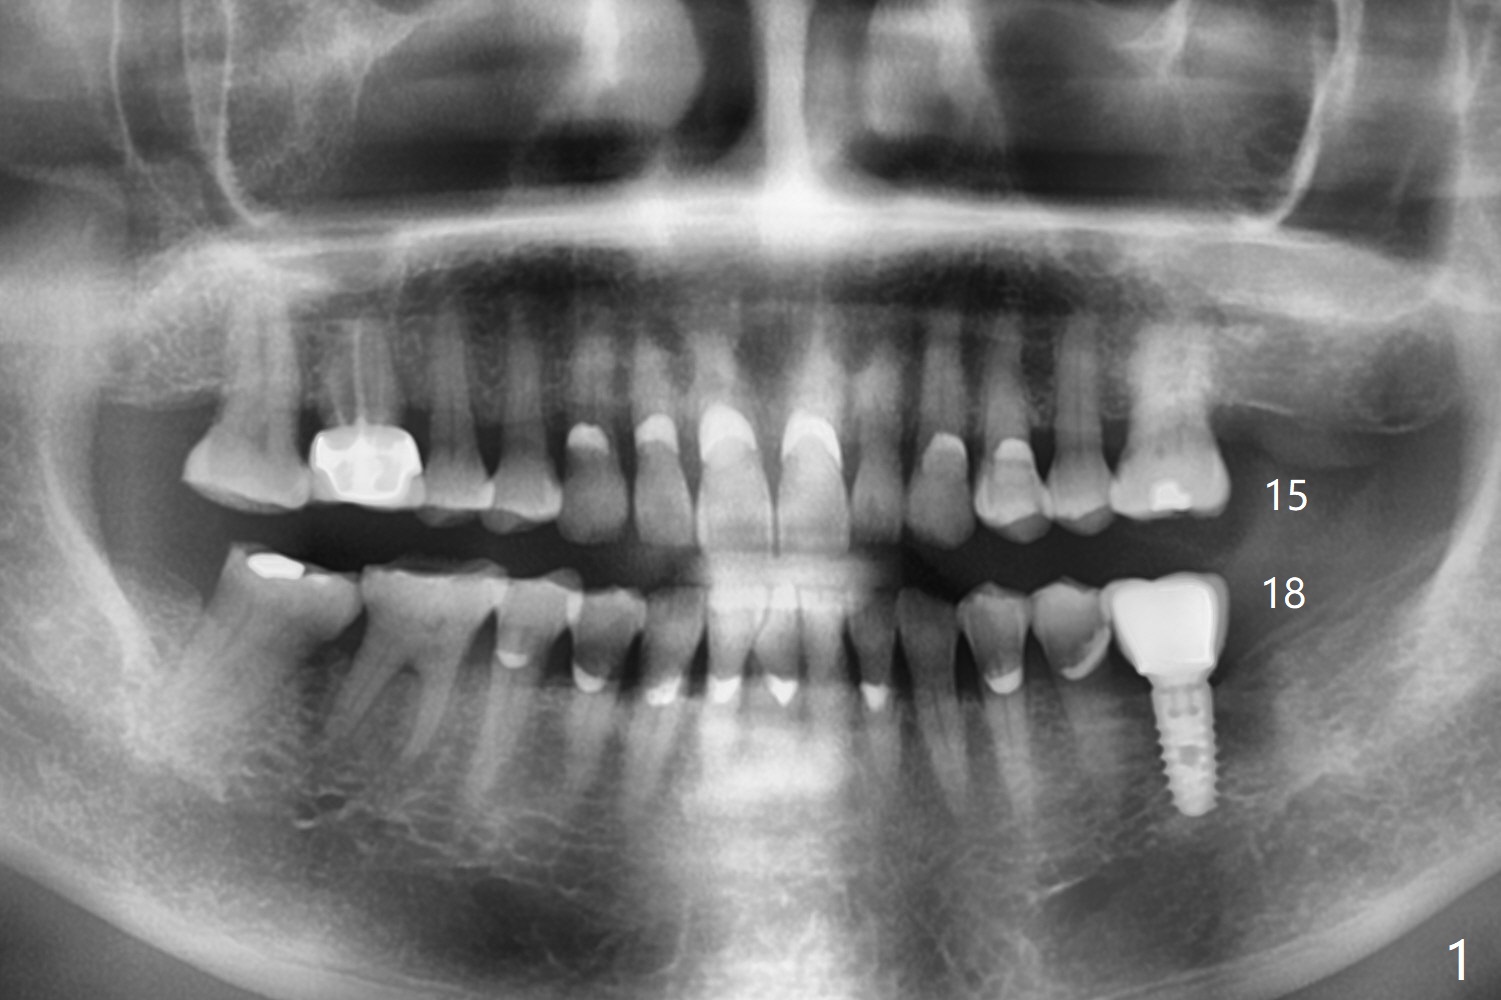

A 73-year-old woman with sign of occlusal wear breaks a lingual cusp of #31. After restoration, she agrees to have implants at #15 and 18 (Fig.1-3).